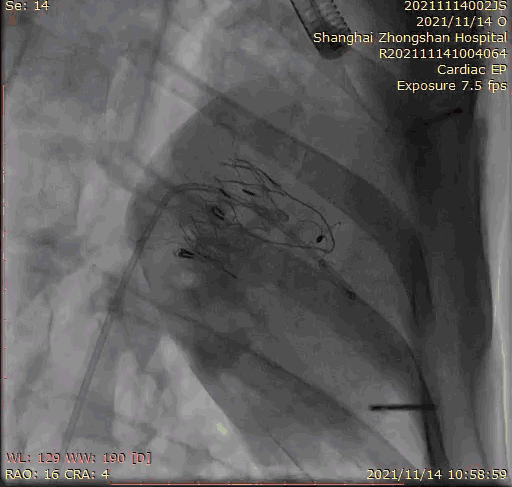

上海中山醫(yī)院葛均波院士、錢菊英院長、周達(dá)新教授、潘文志教授、潘翠珍教授、李偉教授共同完成此次臨床前研究。術(shù)后葛均波院士對Lux-Valve Plus的器械操作性能給予了高度評價,DSA和超聲影像也顯示出在本次研究中Lux-Valve Plus的安全性和有效性俱佳。

本次臨床前研究經(jīng)右側(cè)頸靜脈置入LuX-Valve Plus輸送系統(tǒng)可調(diào)彎鞘管,在DSA及超聲引導(dǎo)下將人工三尖瓣瓣膜植入到原有三尖瓣位置,利用獨(dú)特的錨定技術(shù)將人工瓣膜支架可靠固定在預(yù)定的位置。